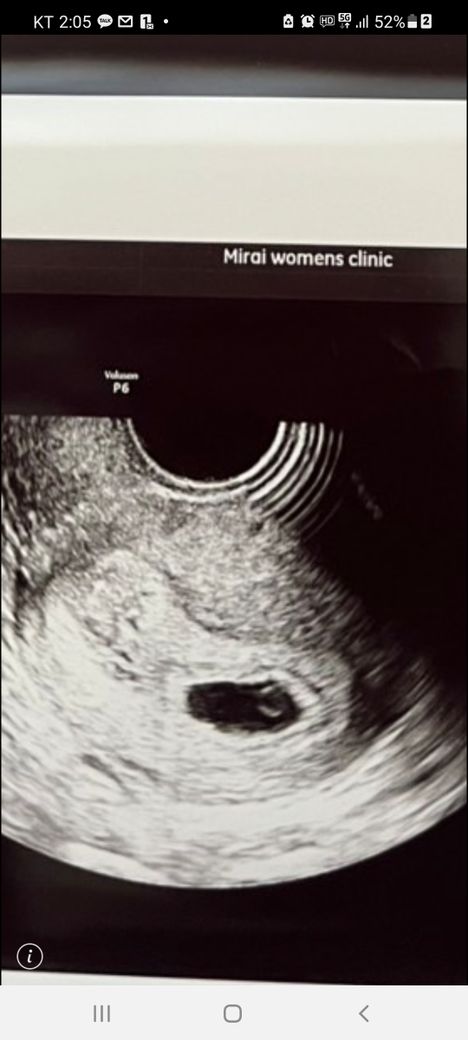

초음파사진 임신 몇주차 인지 봐주세요

초음파사진 첨부합니다

초음파 사진을 보고 임신 몇주차인지

전문가나 경험자 있으시면

알려주시면 감사드리겠습니다.

첨부해주신 사진에는 임신낭과 내부의 난황이 관찰되는 것으로 보이며, 대개 임신 초기인 5-6주 경 관찰되는 소견들입니다. 다만 임신 주수 평가에는 마지막 생리 시작일과 초음파 소견에 대한 평가가 함께 이루어지므로, 산부인과에서 더 정확한 답변을 들어보실 수 있으실겁니다.